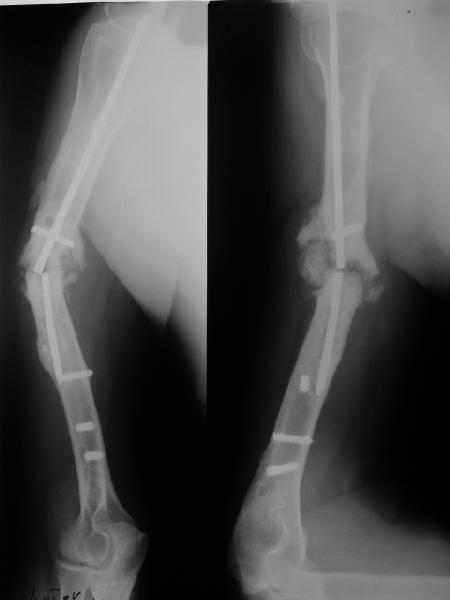

Наверно, можно пойти на укорочение, убрав металлический цилиндр, не такой уж большой дефект. Снимки в чем-то похожего пациента прилагаю - тоже несращение диафиза после многократных операций, и надмыщелковый свежий перелом (случился после удаления обломка стержня аппарата).

Конечно, пьянство с падениями и прочими упражнениями ставит под вопрос любое дальнейшее лечение. Аппарат, что ли, еще и поверх наложить... В качестве внешнего металличкеского каркаса...